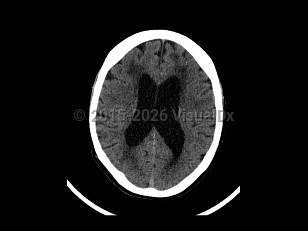

Normal pressure hydrocephalus (NPH) is a common neurologic disorder resulting in slowly progressive gait abnormalities, cognitive deterioration, and urinary incontinence.

The incidence of NPH increases with advancing age, and most patients are over the age of 60. There is no difference in incidence between men and women. NPH has an estimated incidence of 1-5 cases per 100 000 people per year. Its prevalence is reported to be less than 1% in persons under the age of 65, and up to 3% for persons aged 65 or older. Among individuals with dementia, the incidence of NPH is thought to be between 2% and 6%.